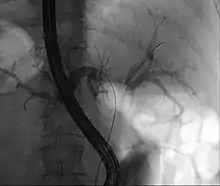

| Klatskin tumor during ERCP. Wires were inserted into the left and right biliary systems. Both parts were injected through a tube with contrast, but there is no contrast visible in the area of confluence of the two systems | |